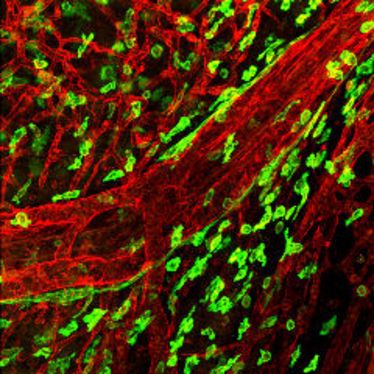

1. Small Animal Imaging Workshop in Münster

1. Small Animal Imaging Workshop in Münster

22.11.2010

- 26.11.2010

1. Small Animal Imaging Workshop in Münster

1. Small Animal Imaging Workshop in Münster

22.11.2010

- 26.11.2010

1. Small Animal Imaging Workshop in Münster

1. Small Animal Imaging Workshop in Münster